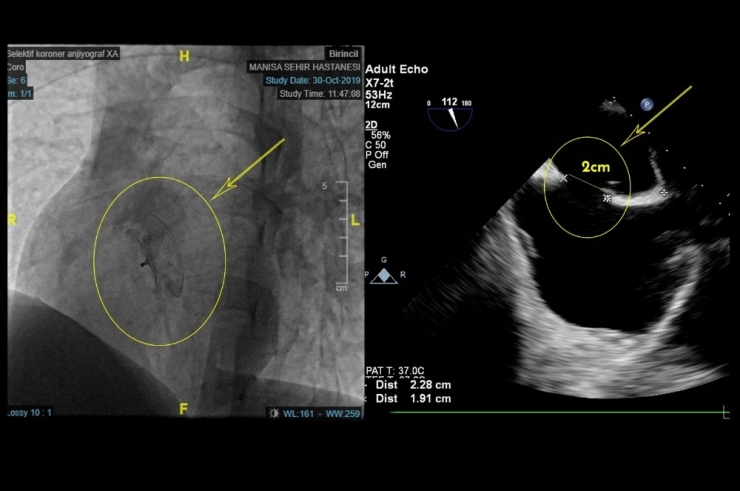

Yaklaşık bir yıldır süren nefes darlığı şikayetleri ile Manisa Şehir Hastanesine müracaat eden hasta Tolga Köz'ün EKO Kardiyografide 2 santimetre genişliğinde ASD (Atriyal Septal Defekt / Kalp Deliği) saptandı. Manisa Şehir Hastanesi Kardiyoloji Kliniğinde gerçekleştirilen işlemin ardından hasta sağlıklı bir şekilde taburcu edildi.

Kalp deliği hakkında bilgiler veren Uzm. Dr. Habil Yücel, "Doğuştan kalbin delik olması yani ASD (Atrial Septal Defekt), kalp kulakçıkları arasındaki duvarda açıklık bulunması durumudur. Bu yüzden akciğerlerde oksijenlenmiş kanın bir kısmı kısa devre yaparak sağ kalbe geçiyor. Bu olay yıllar içinde akciğere giden kanın artmasına, akciğer damarlarında basınç yükselmesine, kalp kasında hasara, nefes darlığına, ritim bozukluklarına ve kalp yetmezliğine neden olabiliyor. Hastalık, çocuklukta belirti verebildiği gibi uzun yıllar hiçbir şikayete neden olmadan da varlığını sürdürebiliyor. Hastamız Tolga'nın da kalbindeki delik yapılan tetkiklerden sonra şemsiyeye benzer birkaç milimlik bir cihazın anjiyoyla yerleştirilmesi sayesinde kapatıldı ve bir gün sonra sağlıkla taburcu ettik." dedi.